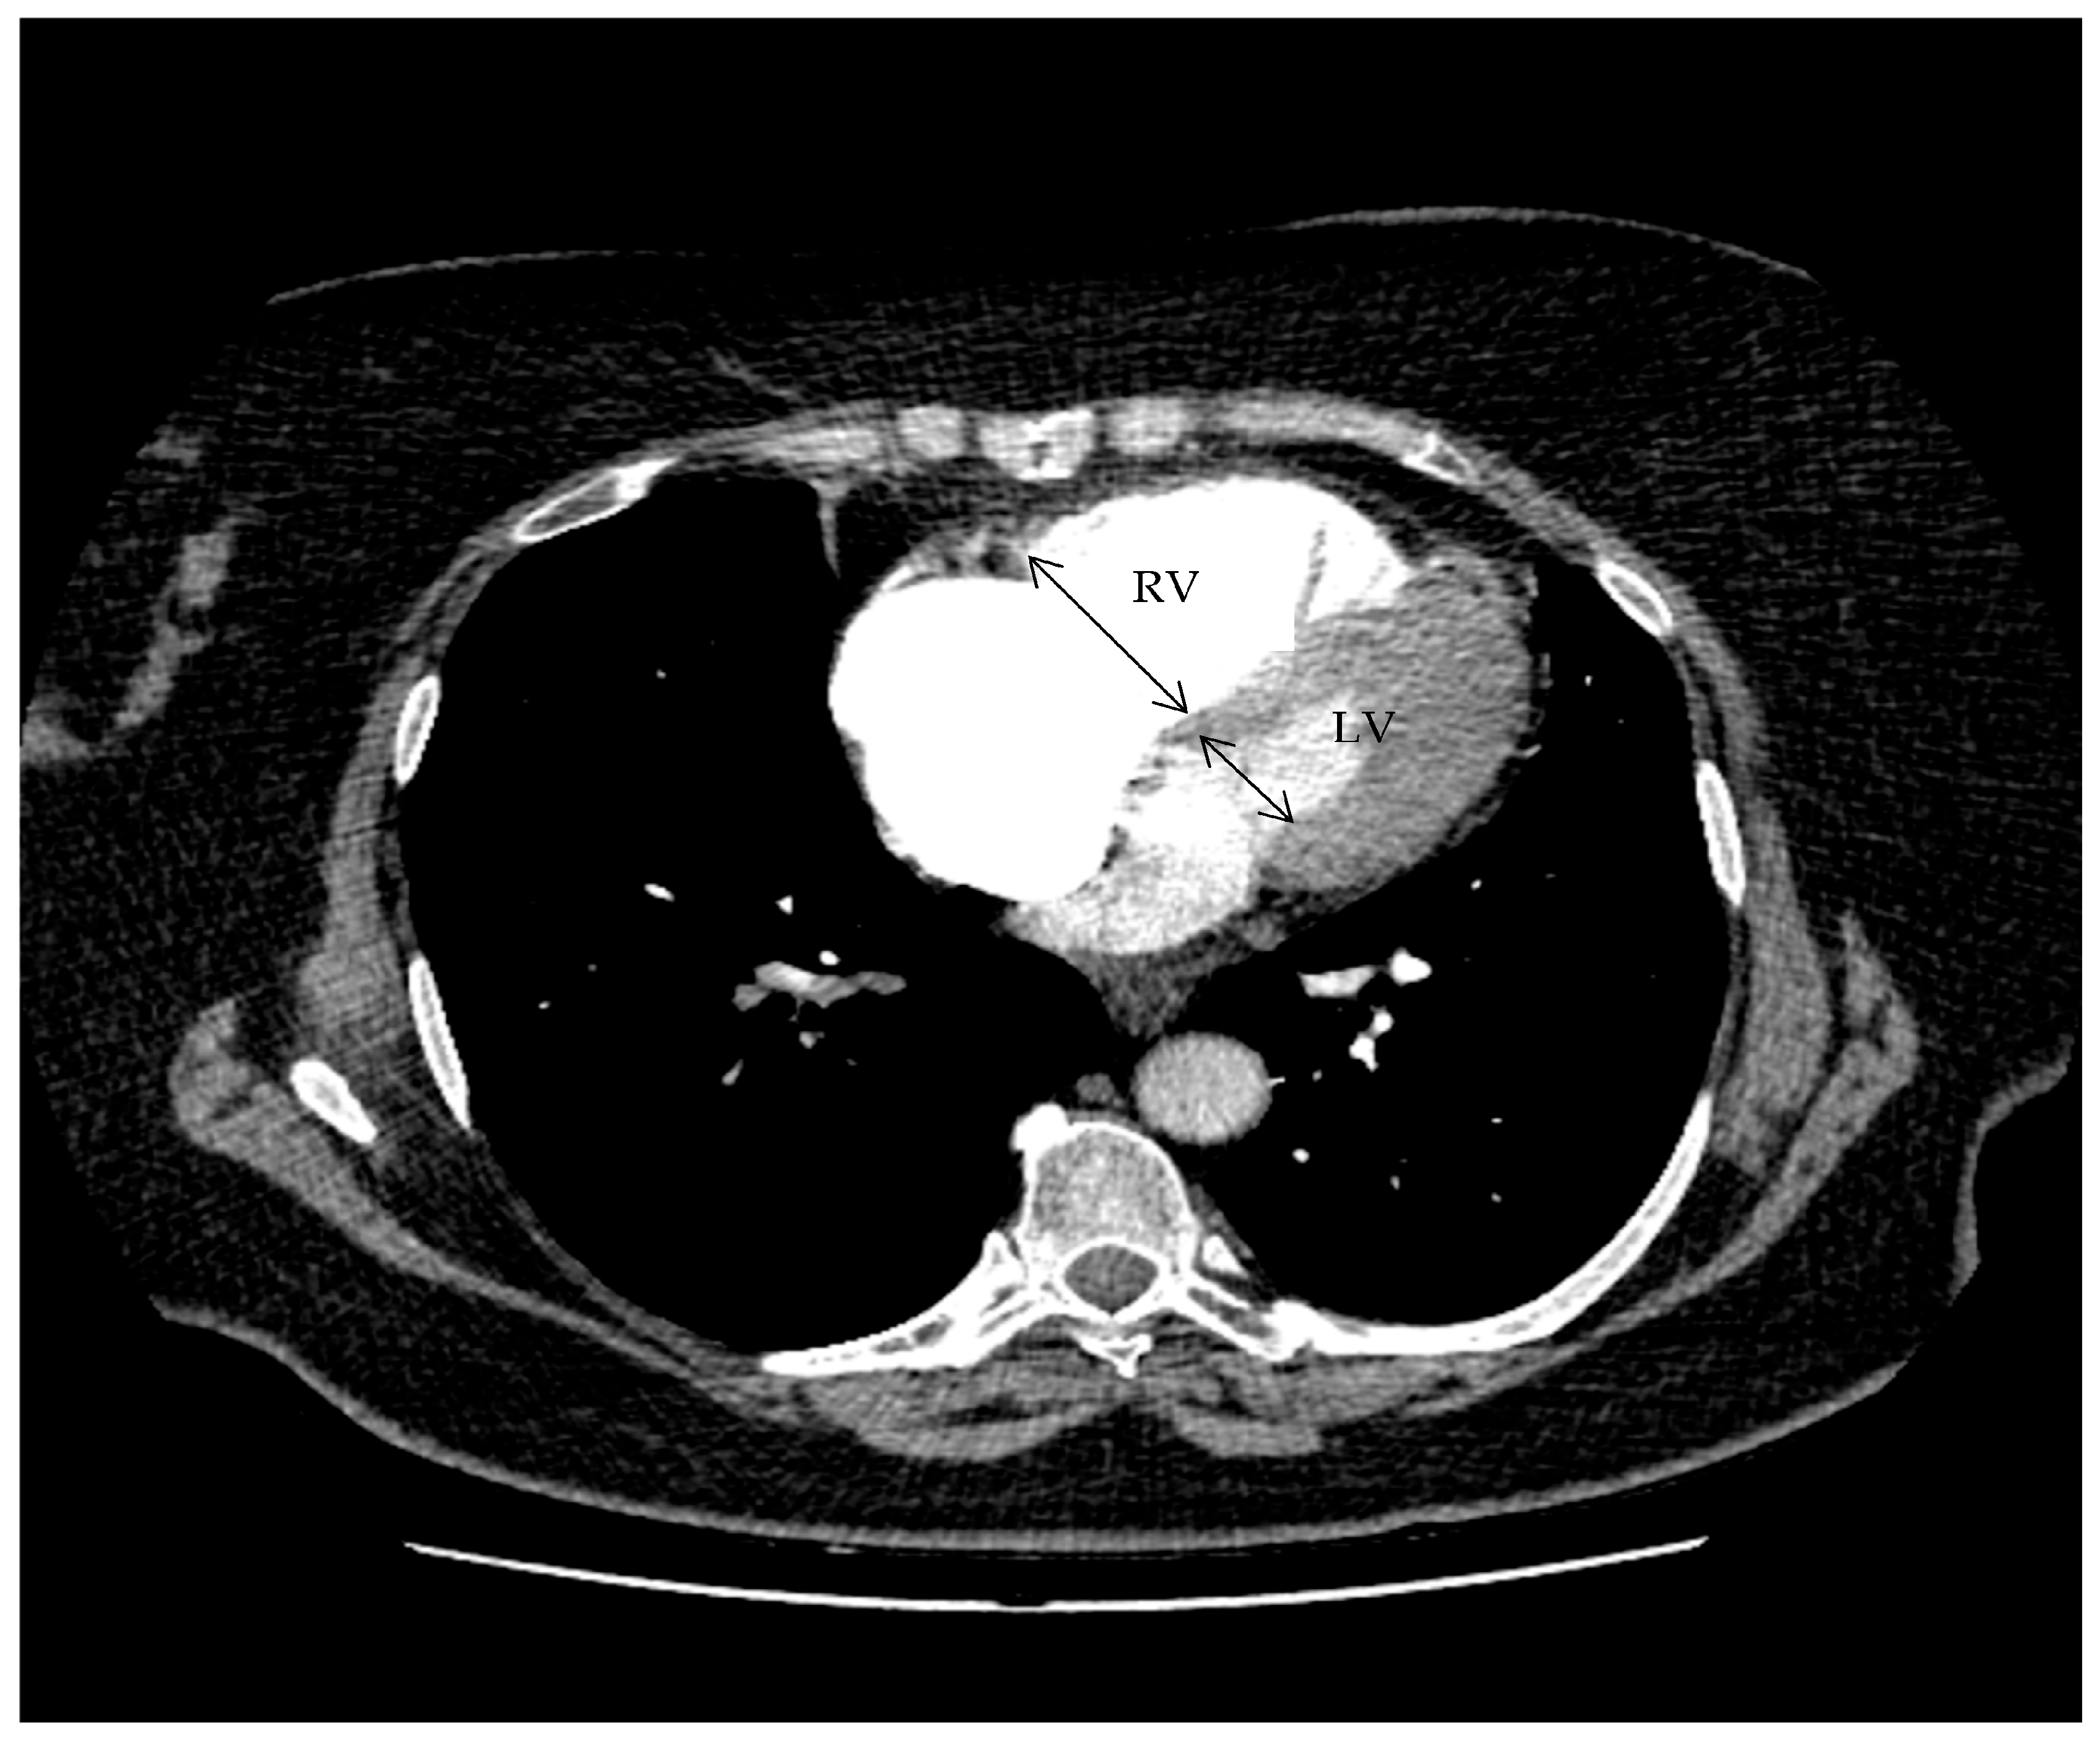

RV/LV diameter ratio: maximum transverse diameter of the right ventricle divided by that of the left ventricle on axial reformats.

The RV/LV diameter ratio was calculated on axial reformatted images as the ratio between the maximum transverse diameter of the right ventricle and that of the left ventricle, measured at the widest ventricular level. Figure 1 indicates the measurement of the right-to-left ventricular diameter ratio on axial CTPA.

Figure 1. Measurement of the right-to-left ventricular diameter ratio on axial CTPA. Axial contrast-enhanced CT image at the level of the ventricles demonstrating measurement of the maximal transverse diameter of the right ventricle and left ventricle. The RV/LV ratio was calculated as the RV diameter divided by the LV diameter.